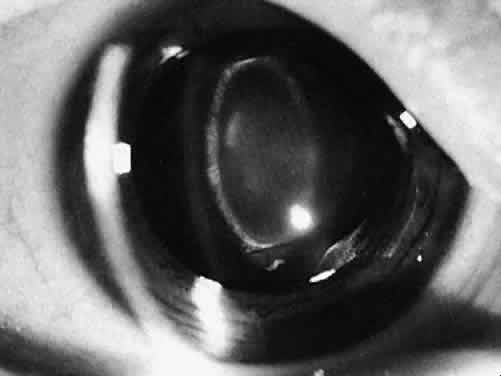

Fig. 15. An eye 6 months after lens aspiration. The posterior capsule was left intact and is becoming opacified. The peripheral lens remnants and lack of synechiae provide support for a future sulcus-fixated intraocular lens if needed.